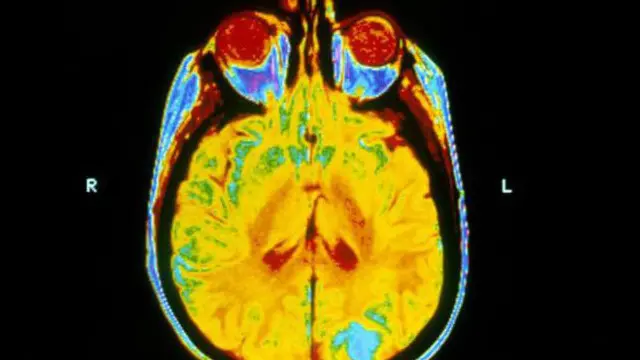

''د دماغ رادیو تراپي د سږو سرطان درملنه کې ګټه نه کوي''

د عکس سرچینه، Science Photo Library

د یوې نوې څېړنې پایله کې ویل شوي، د سرطان هغو ناروغانو ته د بشپړ دماغ له رادیو تراپي نه هېڅ ګټه نه رسېږي، چې د سرطان جرړې یې دماغ ته رسېدلې وي.